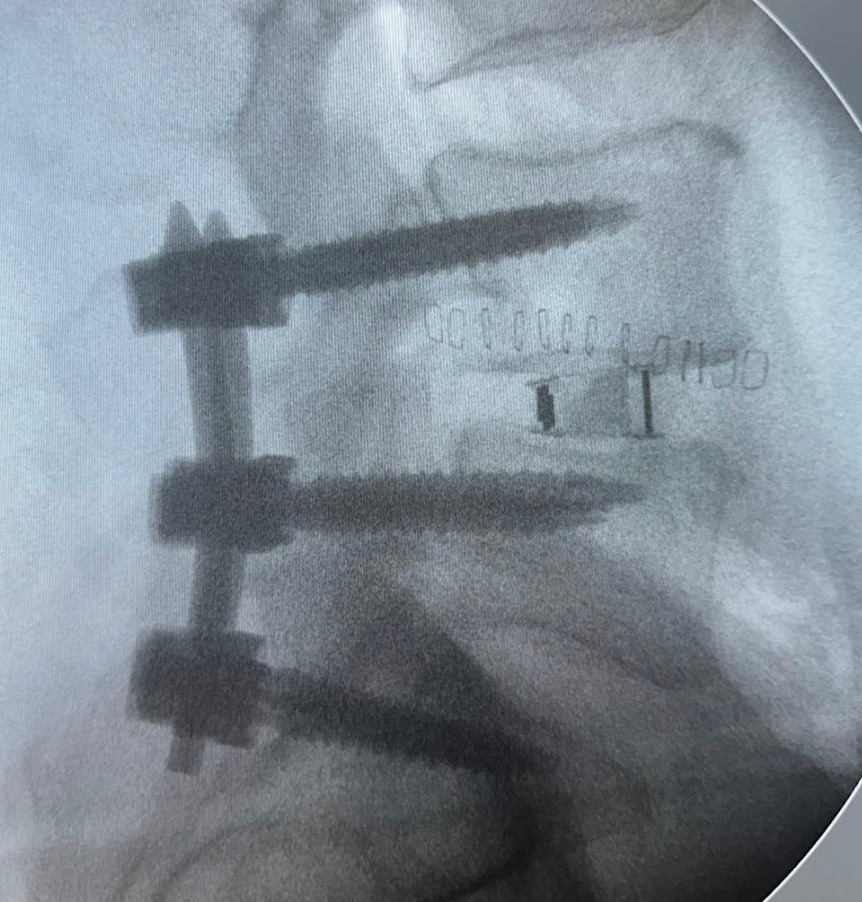

Dr. Vito Lavanga

Ortopedia della Colonna Vertebrale